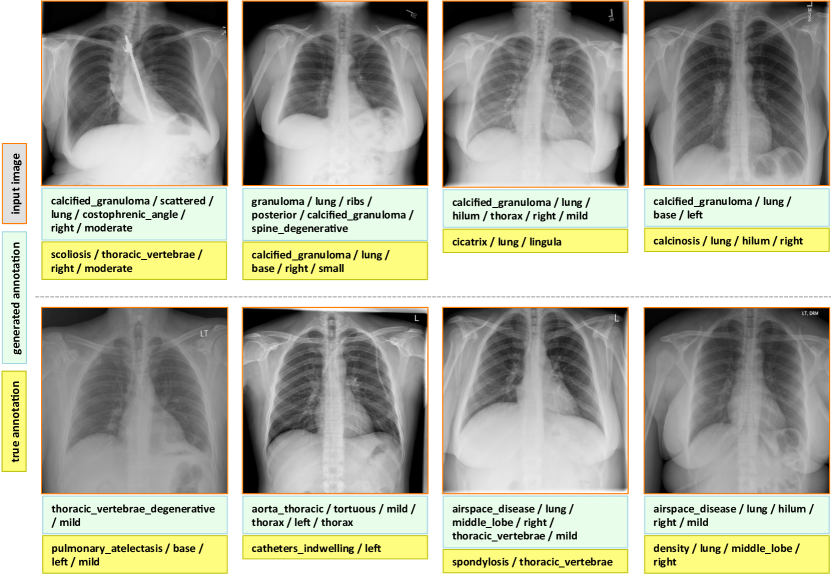

7.1 Evaluation

The final evaluated BLEU scores are provided in Table 5. We achieve better overall BLEU scores than those in Table 4 before using the joint image/text context. It is noticeable that higher BLEU-N () scores are achieved compared to Table 4, indicating that more comprehensive image contexts are taken into account for the CNN/RNN training. Also, slightly better BLEU scores are obtained using GRU on average and higher BLEU-1 scores are acquired using LSTM, although the comparison is empirical. Examples of generated annotations on the chest x-ray images are shown in Figure 6. These are generated using the GRU model, and more examples can be found in the supplementary material.

Appendix C More Annotation Generation Examples

More annotation generation examples are provided in Figures 10 and 11. Overall, the system generates promising results on predicting disease (labels) and its context (attributes) in the images. However, rare disease cases are more difficult to detect. For example, the cases pulmonary_atelectasis, spondylosis, and density (Figure 10), as well as foreign_bodies, atherosclerosis, costophrenic_angle, deformity (Figure 11) are much rarer in the data than calcified_granuloma, cardiomegaly, and all the frequent cases listed in Table 1 of the main paper.